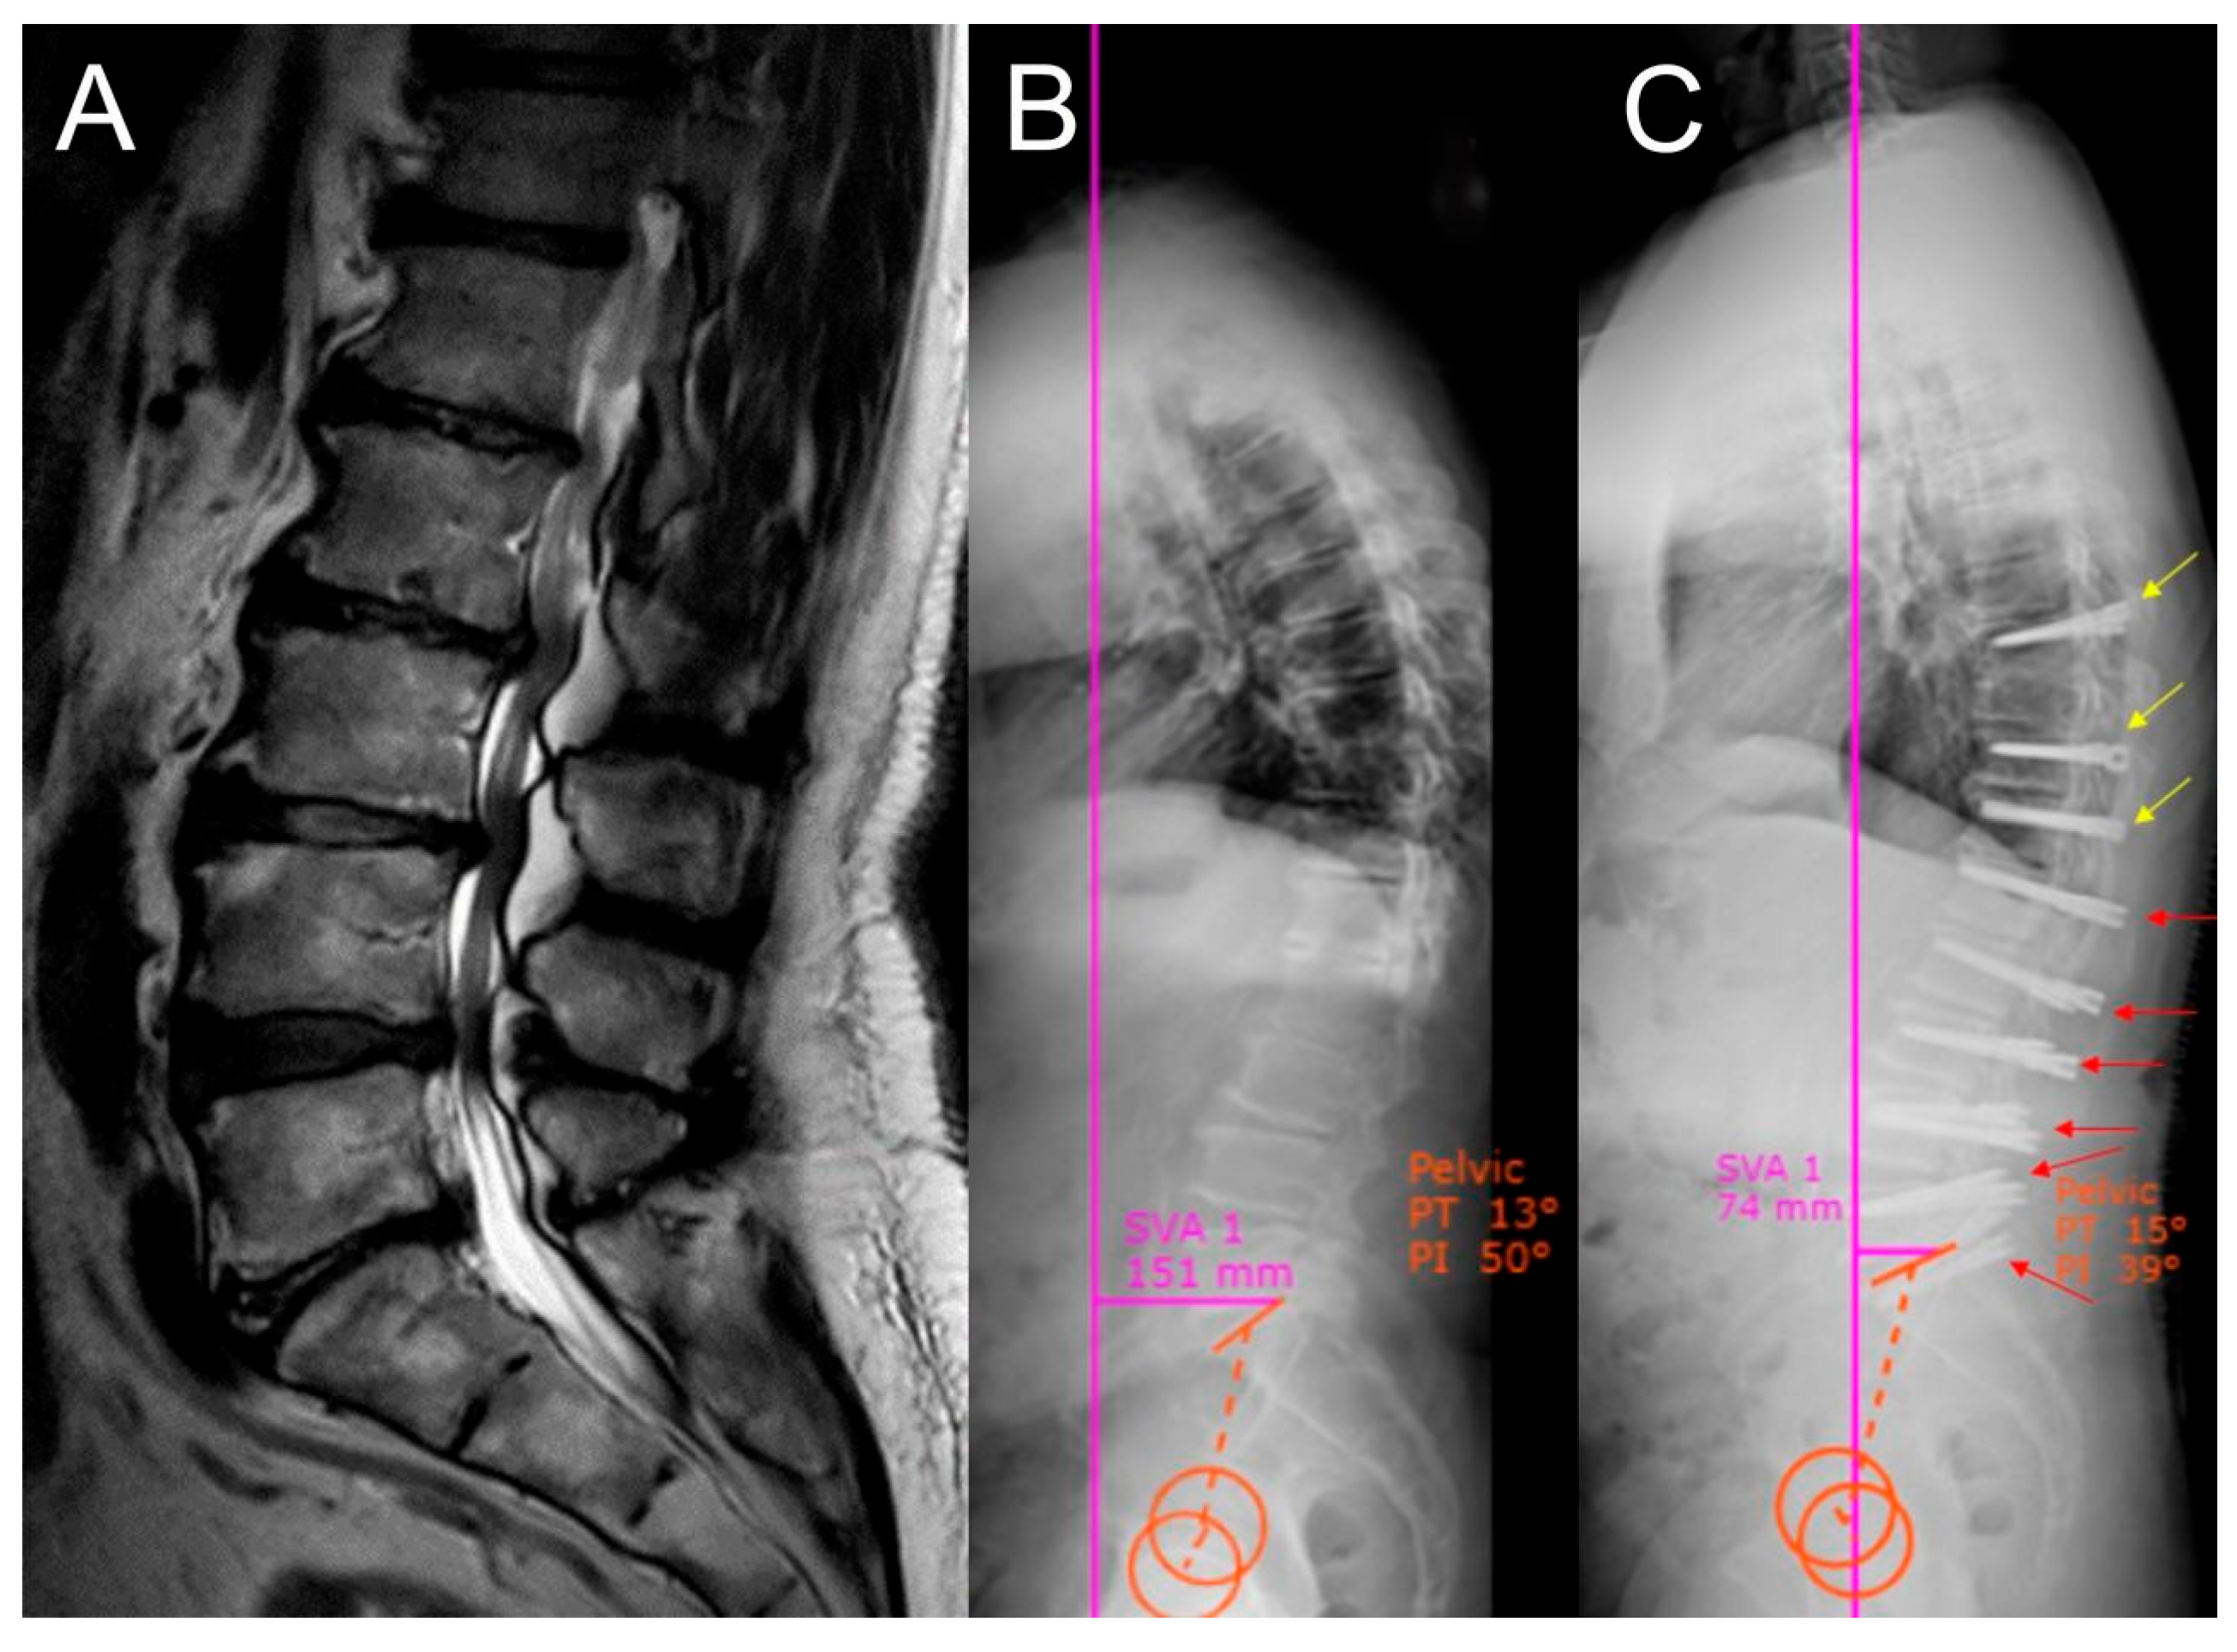

- Ozer, A.F.; Akgun, M.Y.; Ucar, E.A.; Hekimoglu, M.; Basak, A.T.; Gunerbuyuk, C.; Toklu, S.; Oktenoglu, T.; Sasani, M.; Akgul, T.; et al. Can Dynamic Spinal Stabilization Be an Alternative to Fusion Surgery in Adult Spinal Deformity Cases? Int. J. Spine Surg. 2024, 18, 152–163. [Google Scholar] [CrossRef] [PubMed]